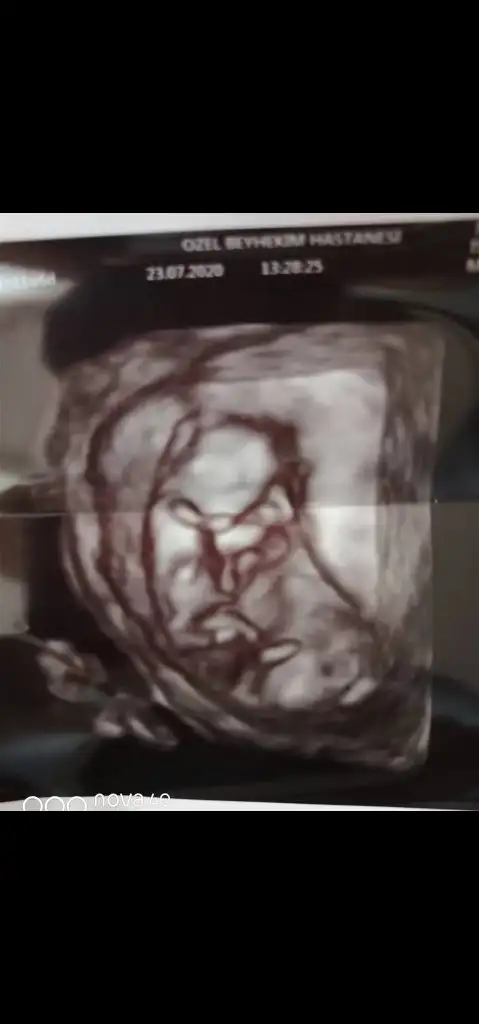

Kız sanki ama nubu ne dik nede paralel poposu yukarı olduğu için etkilemiyorsa kız gibi gibi baska USG de paylaşınCnm arkadaşımın bebeğini yorumlarmısınIkra meyra

Nubu kız gibi görüntüsü erkek gibi

Kız gibi emin olamadım

Başka USG varmı nub kız görünüyor ama emin olamadım ne dik nede paralel iniyor tam karşıya bakıyor cnmYok cnm ya ben yurt dışındayım 20 haftalıkken söylüyorlar burda ondan çok sabırsızlanıyorum